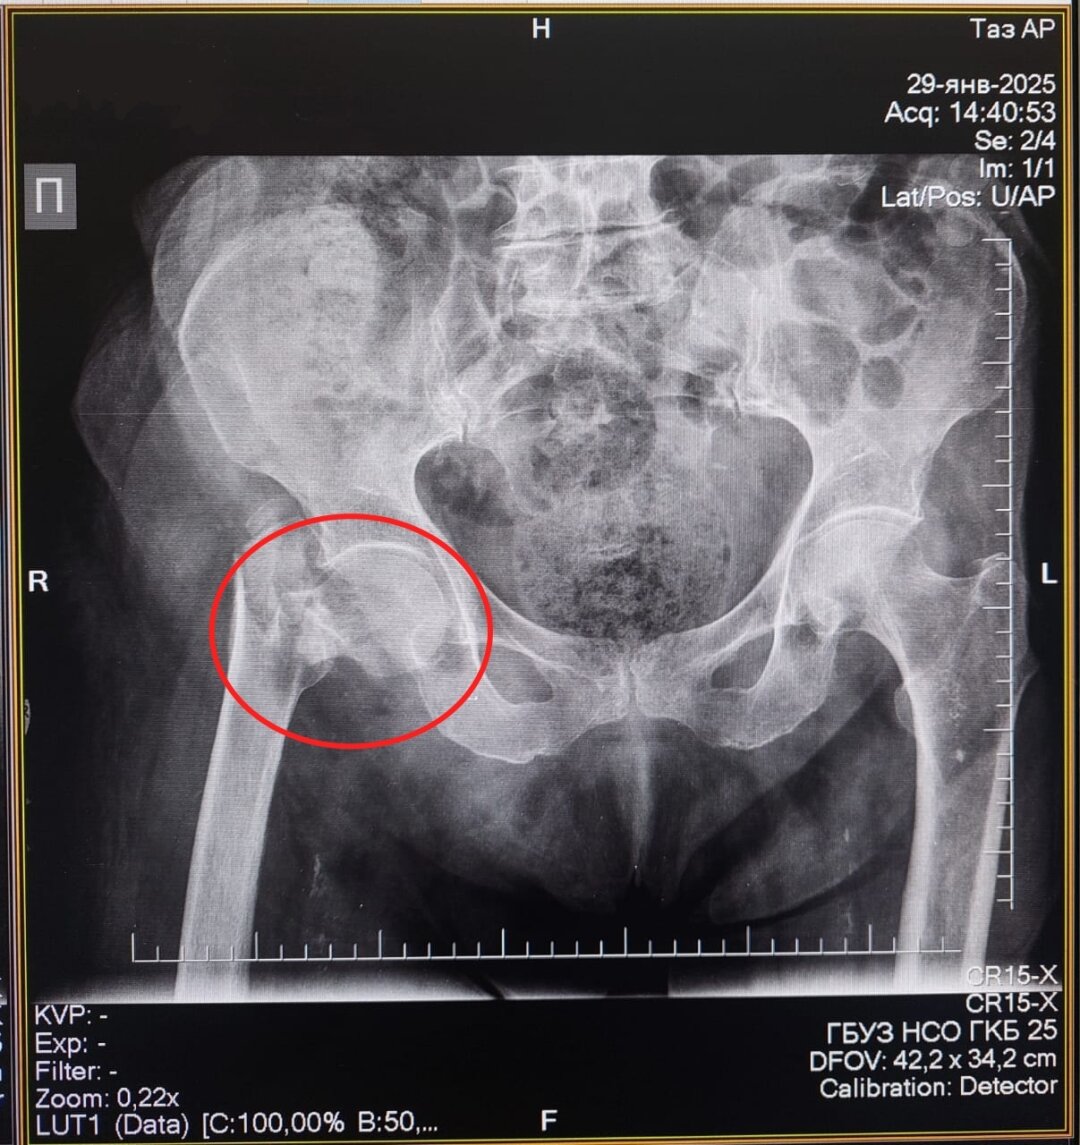

91-летняя жительница Болотнинского района получила перелом проксимального отдела бедренной кости – так эту травму называют врачи – в конце января. Пожилая женщина споткнулась дома о порог и упала.

«В ГКБ № 25 нашей пациентке провели остеосинтез – сопоставили костные отломки и зафиксировали их металлической конструкцией. Сейчас она уже дома, перед выпиской родственники приобрели ходунки. Она уже получает дозированную легкую нагрузку на сустав. В таких операциях даже в 90 лет почему не отказывают? Потому что чем быстрее пациента активизировать, на ноги поставить, тем прогноз благоприятнее», – подчеркивает Абдель Таймусаев.